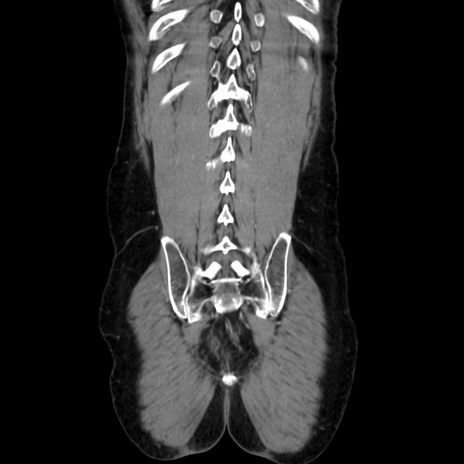

症例37(冠状断像)

【症例】40歳代 男性

【主訴】腹痛

【現病歴】4時間ほど前に電車に乗車中に臍部上より腹痛出現。徐々に増悪し起立困難となり、救急外来受診。生ものは数日食べていない。今朝お雑煮を食べた。

【身体所見】BT 36.8℃、BP 117/84mmHg、HR 91/min、SpO2 97%、苦悶様、腹部:臍上部広範囲圧痛あり、反跳痛±

【データ】WBC 8100、CRP 0.03